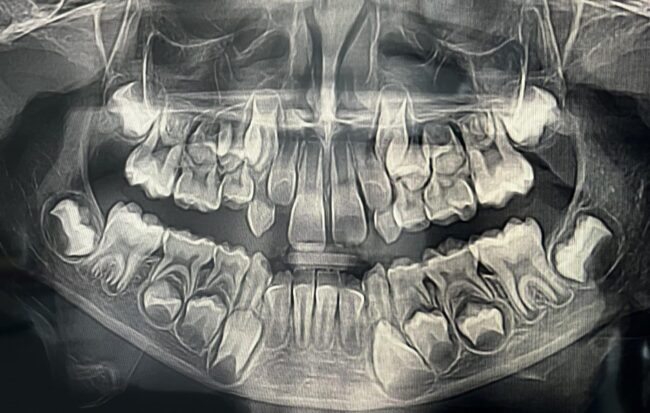

Panorámaröntgen a pontos diagnózishoz lehet fontos, amihez átfogó képet kell kapjunk az állkapcsokról, a fogakról és a környező szájüregi struktúrákról. A panoráma-röntgenfelvételek ebben segíthetnek.

A modern CT-vizsgálat már 3D-képet adhatnak a fogakról, állcsontokról, idegekről és orrmelléküregekről is. Ez a képalkotási módszer lényegesen részletesebb képet nyújt a páciens fogainak és a fogak környezetének állapotáról. Ha lehetőség van rá, akkor ezt alkalmazzuk minden esetben a hagyományos tele- és panorámaröntgen felvételek helyett is. Bizonyos esetekben azonban már nem opciós kérdés, hogy mit használjunk a diagnosztika során.